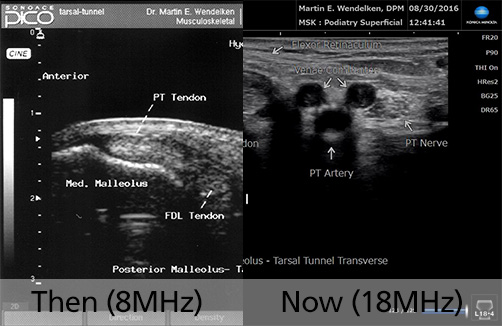

Then (2007) & Now (2020)

8MHz vs 18MHz

• Image 7: Tarsal Tunnel

• Image 8: Transverse 1st MPJ